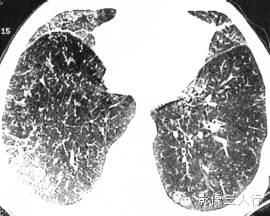

淋巴管转移可为弥漫性或局限性分布,后者位于一侧肺或1〜2个肺叶。常有小叶间隔增厚、支气管血管束增粗。肺内有多发小结节,主要位于胸膜下、支气管血管束周围及小叶间隔。恶性肿瘤的直接蔓延可见肿瘤从原发部位如胸壁、纵隔向肺内侵入生长。

报告书写:胸廓对称,右肺有多发小结节病灶及小叶间隔增厚改变。双侧肺门不大,纵隔居中,其内未见肿大的淋巴结。心脏大小正常,胸壁软组织未见异常(图2)。

图2右肺癌性淋巴管炎